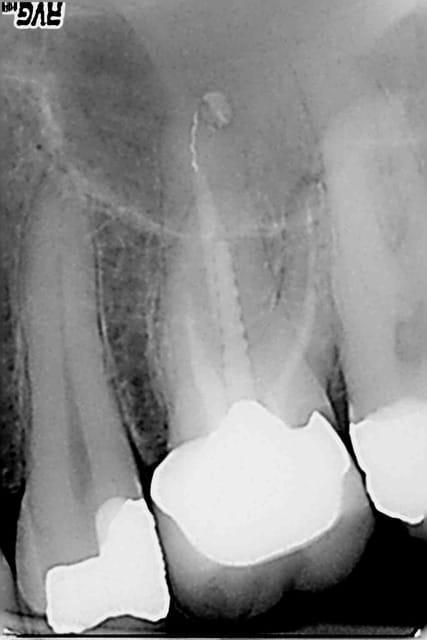

Ceram à refaire sur cette 26 facile : dépose , rectification de préparation empreinte, provisoire ( 20 mn) et pose. Sauf que le sc 33 initial est resté dans la provisoire à la dépose de celle ci.-))

Pas grave j' y ai recollé un screw post titane (screw pol de chez apol) avec du mimesis DC ( composite dual multi usage) après avoir apprêté l'intrados de la couronne et le reste de la dent au peak universal bond.

C'est quoi qui te gène ? Le fait de ne pas se faire chier à faire une RTE ( a vrai dire pas de signe radio de pèche) ? ou de faire un sc33 après la couronne ? -))))

Tu es sur que l'apex de la palatine va bien? Simple question

Elle a l'air très bien cette 26. Je suis sûr qu'elle est comme ça depuis 10 ans. Pas de symptôme, image radio n'est pas préoccupante: j'aurais fait comme l'ingénieux Chicot. En ces temps difficiles, épargner les maigres ressources de l'assurance maladie est un devoir national. Un SC33 au lieu de endo, radios, SPR57, me parait être une conduite de la plus stricte économie. Ceux qui veulent retraiter cette 26 sont de mauvais Français.

Voilà, pas de signe d'appels, la plus stricte économie, pas de signes radios 2D (lol!) et cerise sur le gateau une seule radio post op, gestion en bon père de famille comme ca pas besoin de se rattraper sur la prothèse -))))

Je ne voudrais pas jeter de l'huile sur le feu mais ce qui me gène le plus n'est pas l'éventuelle pêche sur la racine palatine mais plutôt que sur la radio de contrôle la couronne n'est même pas en place avec un hiatus en mésial et une marche en distal.

ça veut dire que le pauvre patient va inéluctablement perdre sa dent dans un délai relativement court soit par carie sous gingivale, soit par problème paro sans parler du manque d'étanchéité du composite et de la perte du point de contact distal.

Edit: et j'avais même pas vu la photo avec la pointe du tenon noircie par la percolation bactérienne dans le canal palatin ... effectivement pas besoin de RTE.

1. Ne pas se fier aux radios dont les images dépendent de l'incidence.

Le soucis, dans le cas présent, est qu'il y aura surement un abcès dentaire dans moins de 2 ans sur cette dent... Du moins c'est fort probable.

Ce gros screw post en se descellant a surement rompu un équilibre précaire qui faisait que cette obturation canalaire médiocre au demeurant n'avait pas déjà eu pour conséquence un joli granulome.

En l'occurence, le reste de gutta du canal a surement été descellé aussi au cours de la manœuvre.

Et cela aboutira dans quelques mois à ce qui est communément appelé une pêche...

Je trouve juste que tu as pris un risque sur ce coup là. Autant, je suis contre le retraitement systématique (quand il n'y a pas de symptôme), autant lorsque je me retrouve dans le canal et qu'il est mal obturé radiologiquement parlant, je pense que pour être plus serein, il vaut mieux retraiter...